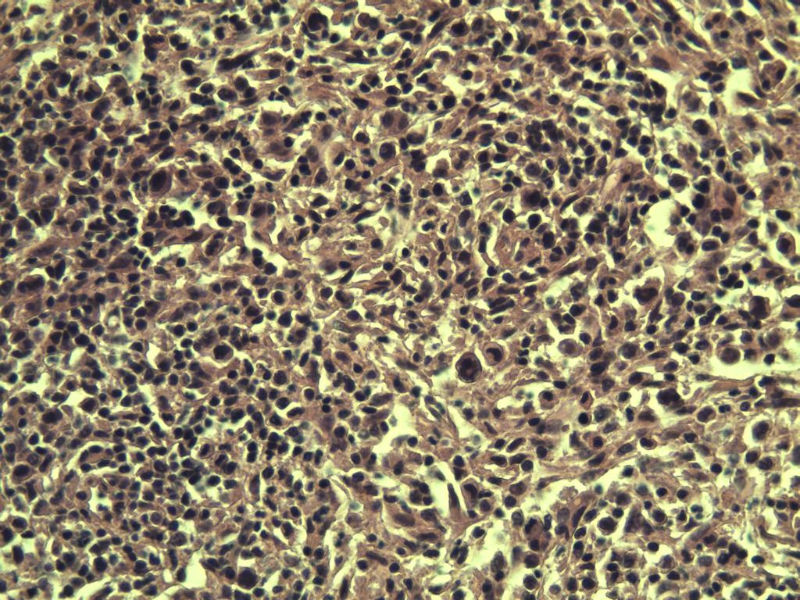

男,38岁,腹股沟 多枚淋巴结活检  直径 0.2-0.5 请各位老师看看 是什么 谢谢了!

"畏寒,发热咳嗽1年,加重伴腹部疼痛2月" 2月前患者感腹部疼痛不适伴大便呈稀大便,量不详,伴腰骶部疼痛,胸片:纵膈及右肺门多发性淋巴结肿大,进一步完善胸部CT:右肺及中叶病变,纵膈及肺门多发淋巴结肿大,结核性可能,脾脏增大,PPD(-),1个月来患者出现中上腹食欲不振,体重进行性消瘦,全身疲乏无力,3天前到医学院就诊,腹部B超:右肝囊肿,胆囊壁毛糙,脾大,胰周多个减弱回声,淋巴结不能除外,腹水,血常规示:WBC16.36x109 /L,N%14.25%,RBC2.63x1012/L ,HGB 66g/L 。右侧腋窝及腹股沟可扪及多枚淋巴结,压痛,无明显粘连。

腹股沟 多枚淋巴结活检图2

副皮质区增生,纤维化显著,细胞呈多形性,有一些多核巨细胞及一些异型细胞,病理性核分裂易见,胞浆红染,散在的小淋巴细胞,T细胞淋巴瘤不能除外,树突细胞肉瘤等鉴别。免疫标记。CD21、CD3、CD5、CD10、CD20、CD79a、PD1、CD68、CXCL13、KI-67、CD68、CD163等,据切片选择。不知对否。

淋巴结正常结构破坏,可见大的异型细胞,上皮样或梭形,恶性肿瘤,依据病史,首先考虑淋巴造血系统疾病,大中小细胞混杂,大细胞多,形态多样,可见多核瘤细胞,除以上考虑外需鉴别间变大、组织细胞肉瘤、指状突/树突细胞肿瘤、HL等,还需排除肉瘤或癌转移,尽管病人年轻,加上ALK、CK、S-100、CD1a。